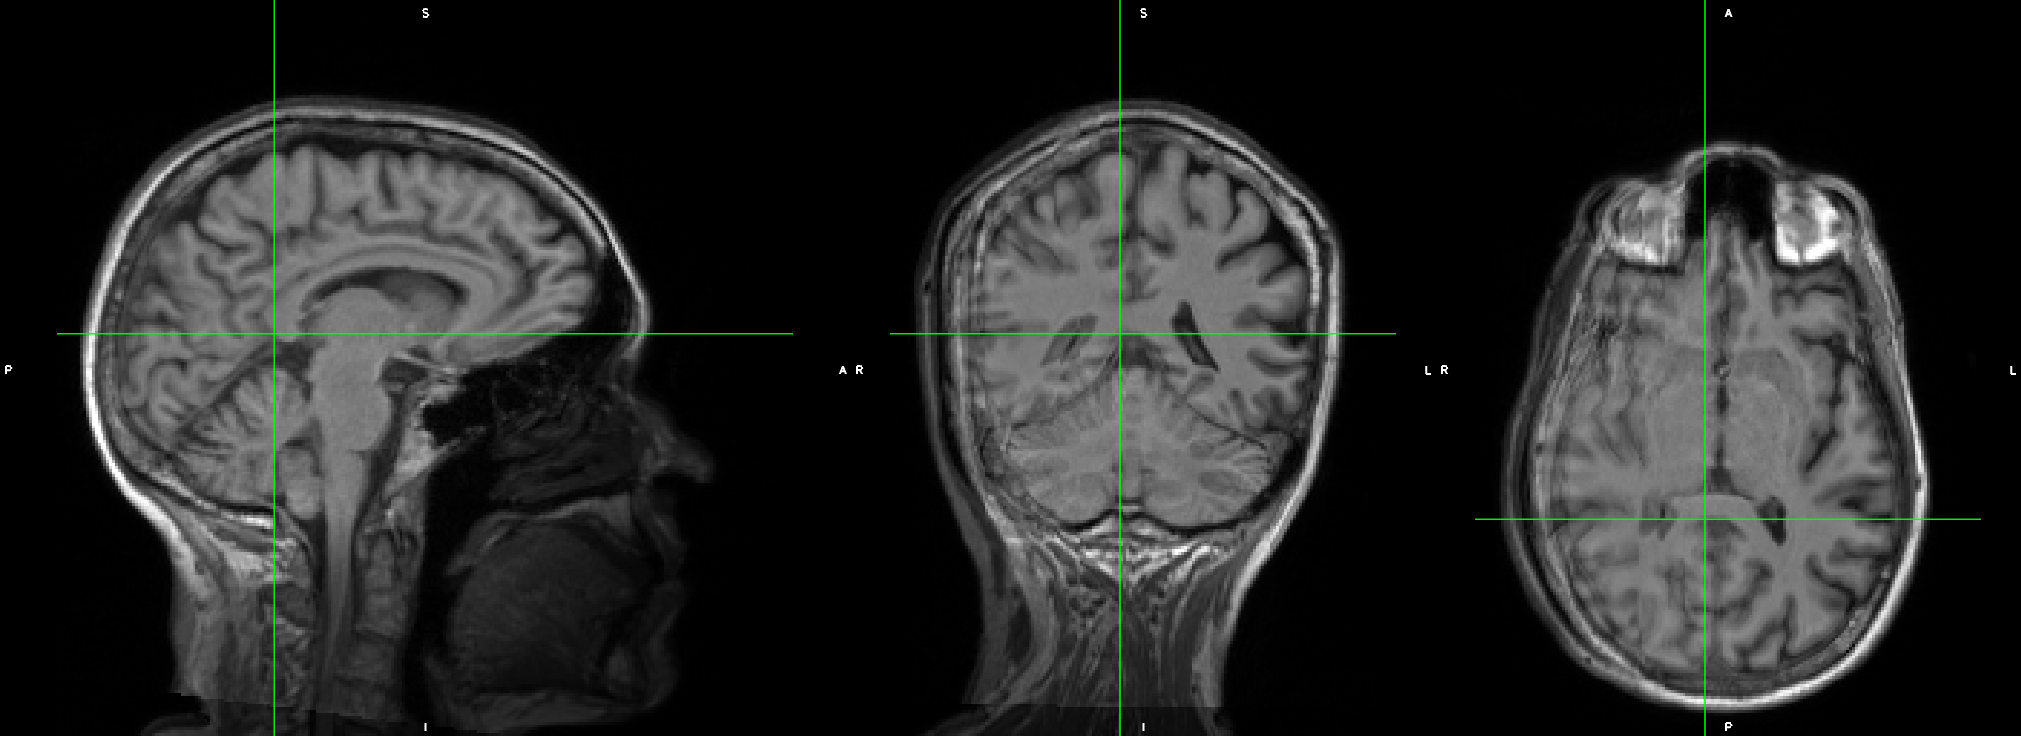

The original T1w image looked perfect, with no artifact, no head motion. But in the _desc-preproc_T1w.nii.gz, the image looked like it had two brains overlapping.

This is the _desc-preproc_T1w.nii.gz

fMRIPrep will use all available T1s (even from different sessions) to create the T1 reference. Do these images look different or were they acquired differently?

They were acquired at each visit separately so yes, there is some displacement between these two.